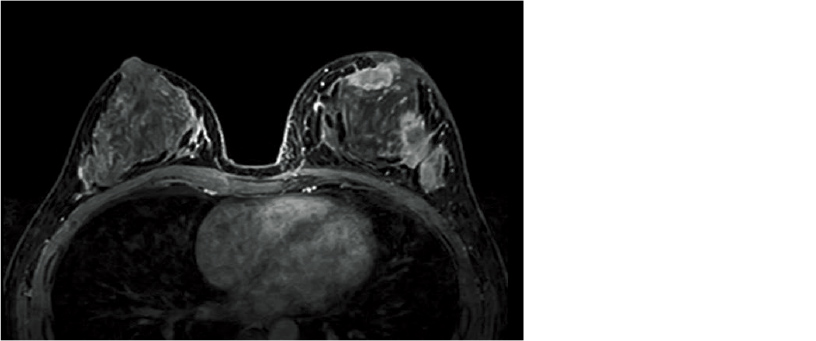

The use of TIGRE enables dynamic imaging in organs such as the liver. The large fat component in the abdomen and breast regions require high-precision fat suppression. We have realized uniform fat suppression effects and dynamic imaging in the abdomen and breast through combined use of high uniformity of the static magnetic field and H-Sinc which corrects for RF non-uniformity.

Breast TIGRE image